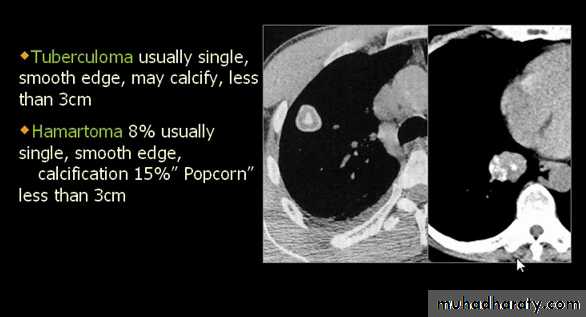

Differential diagnosis of multiple spherical lesions:

1 - Metastasis.

2-Hydatid cyst.

3- Sarcoidosis.

4- Rheumatoid nodules.

5 – pneumoconiosis

6- Histoplasmosis

Chest X-ray shows radio-opaque (white) nodular lesion in the right mid-lung field.

Dx:x chicken pox , Histoplasmosis (calcified granuloma).

Tuberculoma